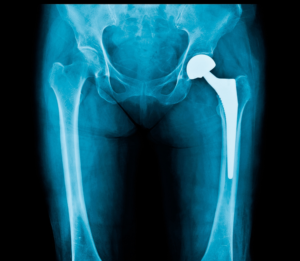

What Happens During Hip Replacement Surgery?

• The damaged ball (top of the thigh bone) is removed

• A new artificial ball and socket are implanted

These components are designed to work smoothly together and reduce pain.